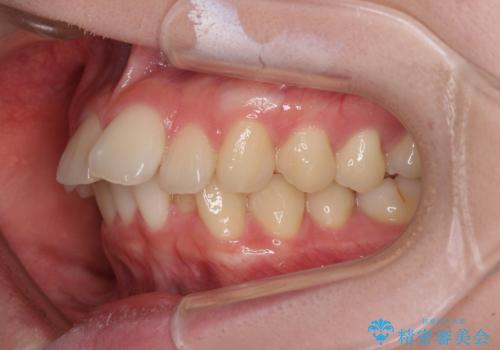

- 下顎の前歯が上顎の歯肉に咬みこむくらいに突出した上顎前歯を気にして来院された患者様です。

口元の突出感はないものの、上顎前歯が前方に傾斜して突出しており、前後に大きなズレがあり非常に深い咬み合わせとなっていました。